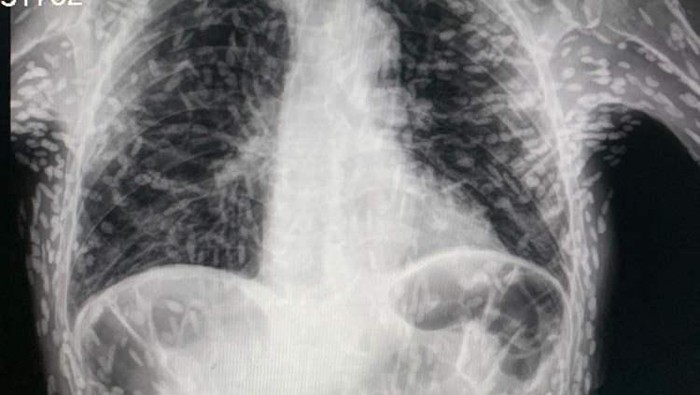

Dr Vitor Borin de Souza, seorang petugas medis di Rumah Sakit das Clínicas, Brasil, membagikan gambar hasil x-ray pasiennya di Twitter. Dalam gambar tersebut, terlihat ratusan titik terang yang merupakan kalsifikasi dari sisa-sisa parasit cacing pita.

"Sistiserkosis diperoleh dari konsumsi telur cacing pita.Tidak ingin mengalami itu? Cuci makanan Anda dengan baik sebelum dikonsumsi," tulis Dr Souza, dikutip dari Daily Mail.

Ini disebut sistiserkosis, yaitu ketika larva dari spesies cacing pita yang biasanya hidup di usus, memasuki jaringan seperti otot atau otak. Larva tersebut membentuk bintil keras seperti kista yang terasa seperti benjolan di bawah kulit.

Kondisi ini umumnya tidak berbahaya karena larva tidak bertahan hidup. Namun, kista yang tersisa dapat menyebabkan masalah jika berkembang di otak atau mata.